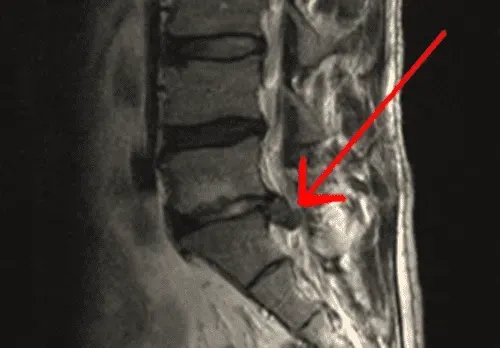

An MRI can reveal a variety of conditions that may be causing sciatica. For example, a herniated disc, which occurs when the soft center of a spinal disc pushes through a crack in the tougher exterior casing, is a common cause of sciatic nerve pain.

An MRI can also show spinal stenosis, a narrowing of the spinal canal that compresses the nerves. Other detectable conditions include spondylolisthesis (slipped disc), degenerative disc disease, and in rare cases, tumors or infections.